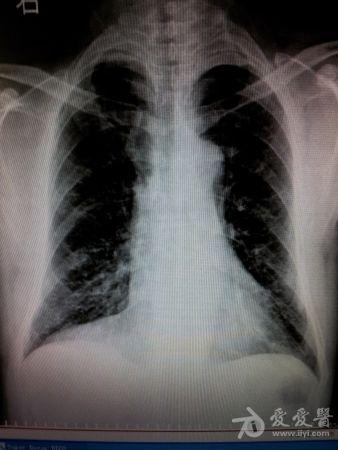

男,52岁,右心膈角是什么?

超越心包位置太多了,明显靠外了。肯定不是心包脂肪垫。如果的一个侧位就好了。提出一个可能“波浪膈”。欢迎质疑。

三角形的,结合透视看看,肺部张不能除外的。

同意楼上,心包脂肪垫。